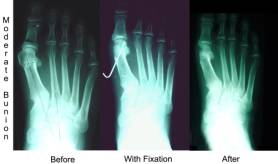

If your IM angle measures 11-14 degrees we call this a moderate bunion. If you just take off the bump as a simple bunion then the chances of the bunion reoccurring increases. We want to try to decrease this angle. We try to move the metatarsal head closer to the second metatarsal. This effectively reduces the IM angle by up to 4 degrees. There are sometimes additional corrections needed to straighten the big toe. By moving the head of the metatarsal over in a moderate bunion the recurrence rate goes down drastically. Usually this requires you not to walk on the foot for a period of 10-21 days.